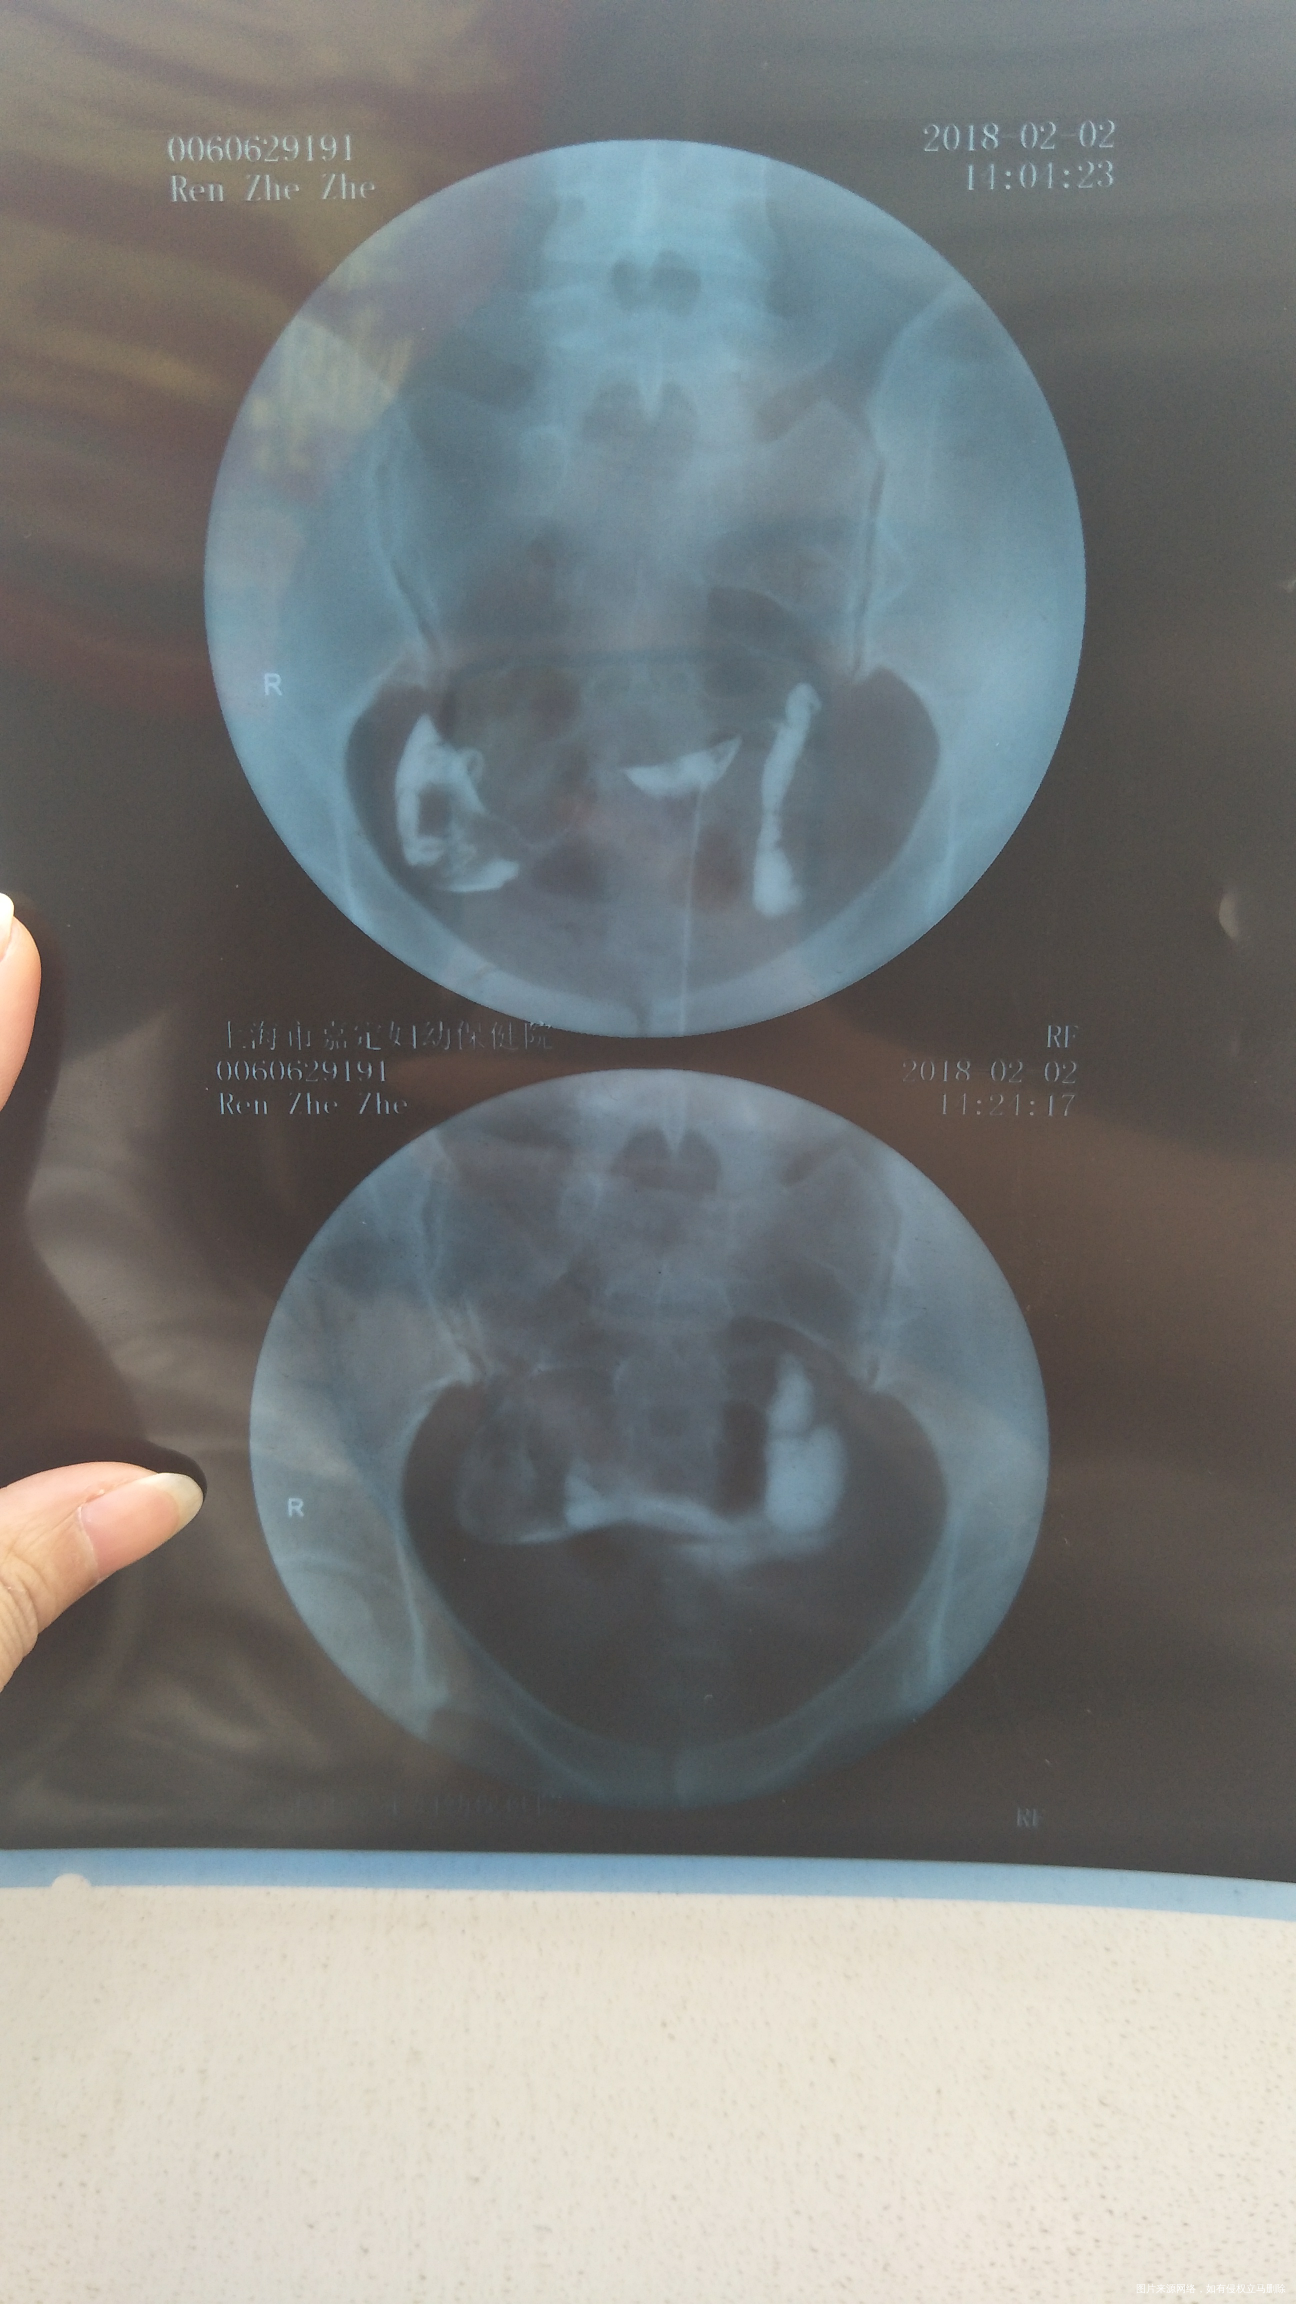

罗棹文

看着输卵管有积水,盆腔有粘连,建议行腹腔镜疏通输卵管,前提是您卵巢储备功能好,男方精液正常,如果卵巢储备功能不好,男方精液不好需要综合评估,必要时行试管婴儿助孕,祝您好孕,欢迎咨询,满意请点击采纳

输卵管有积水,盆腔有粘连,建议行腹腔镜疏通输卵管

你好,输卵管有积水,盆腔有粘连,建议行腹腔镜疏通输卵管

建议行腹腔镜疏通输卵管